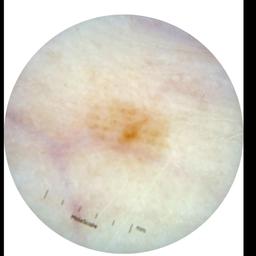

ISIC_0301375

1986 x 1986

acquisition_day 331

age_approx 35

anatom_site_1 Trunk

anatom_site_2 Anterior trunk

anatom_site_general anterior torso

diagnosis_1 Benign

diagnosis_confirm_type single image expert consensus

image_type dermoscopic